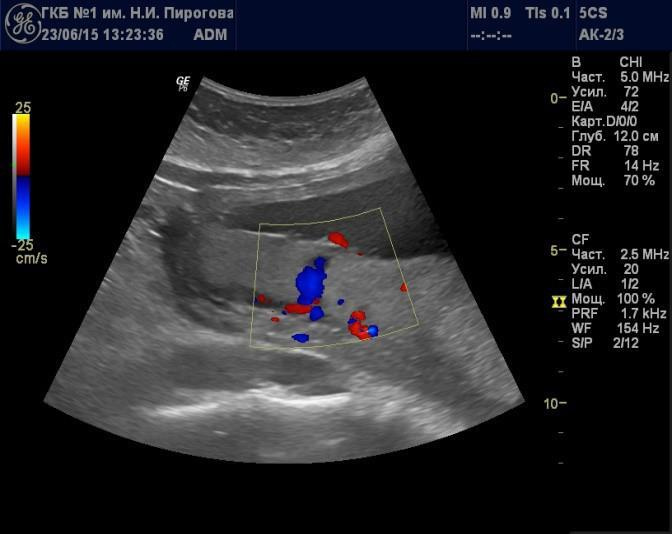

Выявляемые при серошкальном исследовании плаценты ан- или гипоэхогенные зоны чаще всего являются эхографическими срезами участков расширения ее МВП (Рис. 7) и значительно реже сосудов плода (Рис. 8). Расширение МВП может быть связано как с поступлением материнской артериальной крови, и отражать одно из состояний артериального капиллярного русла маточно-плацентарного кровотока (Рис. 9), так и с оттоком в материнское русло венозной крови (Рис. 10). При этом направление тока крови может быть установлено при цветовом допплеровском картировании (ЦДК). Следует иметь в виду, что венозное звено маточно-плацентарного кровообращения состоит из двух функциональных частей: венозных коллекторов плацентарного ложа возле разделительных септ и краевых синусов [10], которые также могут быть расширены (Рис. 11).

Рис. 9. Беременность 24 нед. Расширение межворсинкового пространства, связанное с артериальным притоком, в серошкальном режиме (а) и режиме цветового допплеровского картирования (б).

Рис. 10. Беременность 20 нед. Расширение межворсинкового пространства, связанное с венозным оттоком, в серошкальном режиме (а) и режиме цветового допплеровского картирования (б).